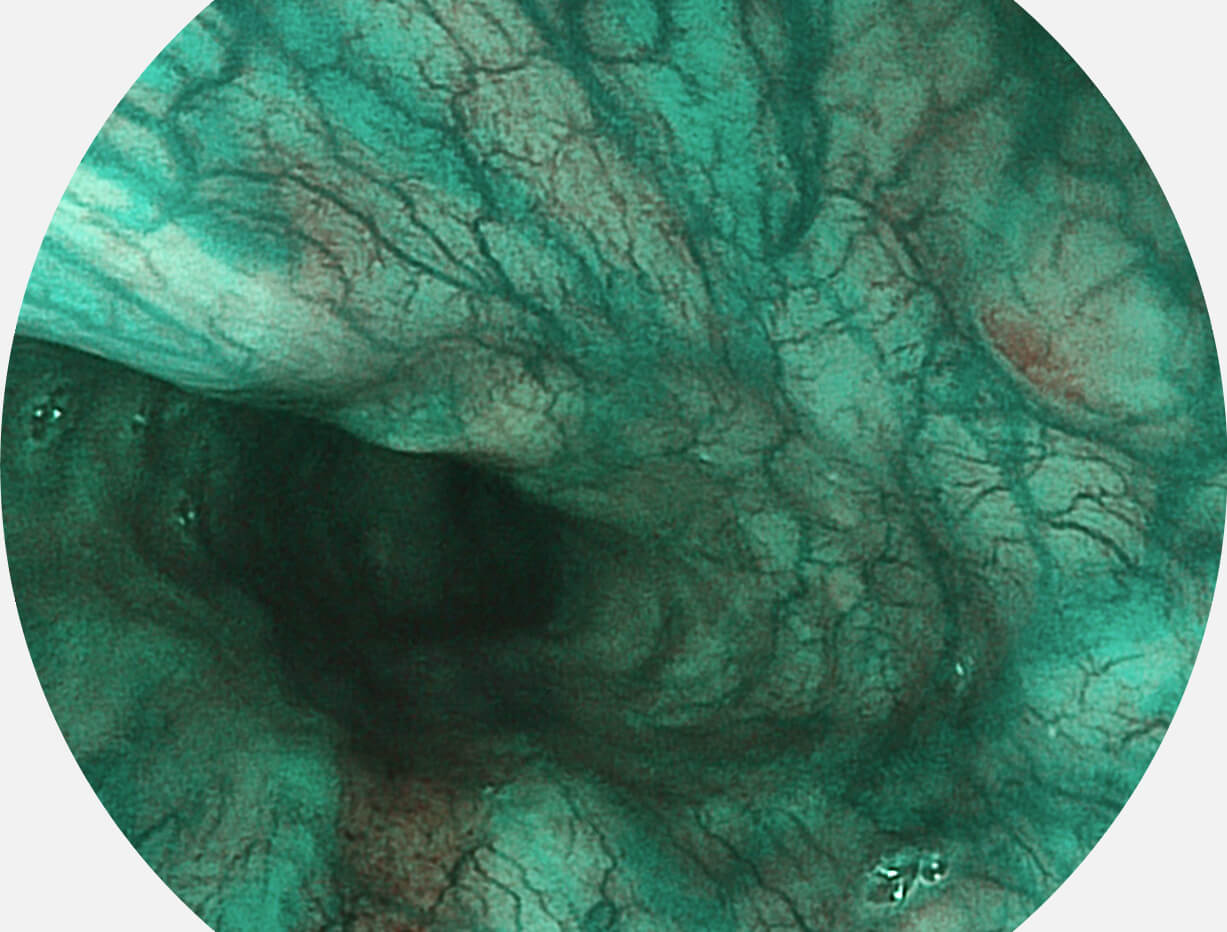

Spectral Focused lmaging, SFI

图像具有高亮度、高黏膜血管颜色对比度的特点,且不改变粘液、食物残渣、粪便的基本颜色,可在中远景下进行观察,助力消化道早期疾病的诊断。

• 白光图像 SFI图像